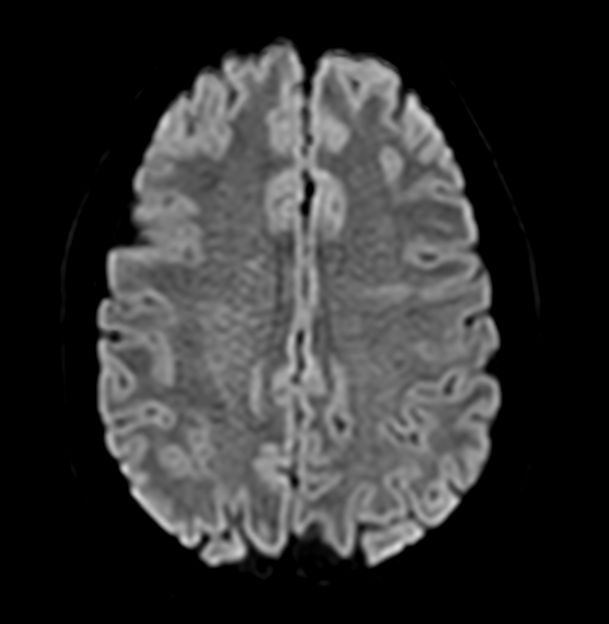

Axial Diffusion (b1000)

-